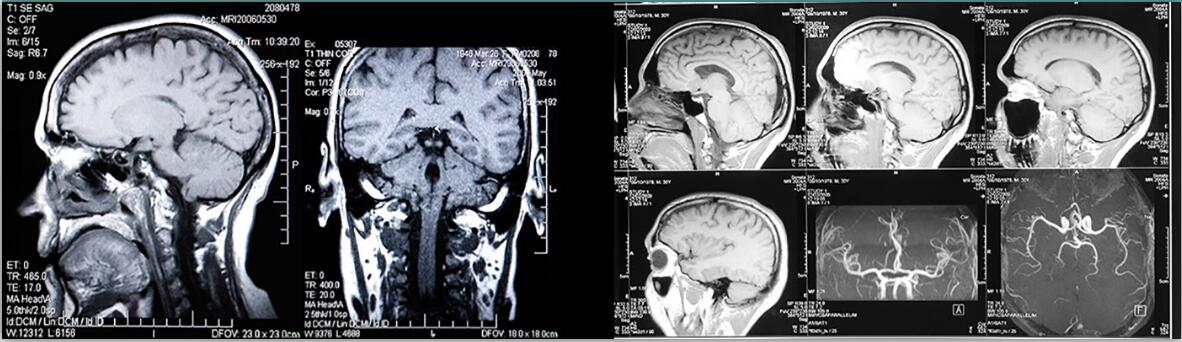

●定制患者特定硅膠血管模型服務(wù)

專注于創(chuàng)建定制或患者特定的硅膠血管模型。您向我們提供感興趣的脈管系統(tǒng)的 STL 文件,我們將進(jìn)行報(bào)價(jià)。我們可以修改脈管系統(tǒng)(即改變壁厚,加長(zhǎng)血管,為了連接目的使血管變細(xì)……使其適合帶有連接器的矩形盒子。我們可以添加狹窄或動(dòng)脈瘤,改變病理的大小和形狀……